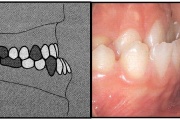

) Röntgenülesvõte. Ülemise esimese jäävmolaari lõikumine on takistatud 2. piimamolaari tõttu

Esimese jäävmolaari ektoopiline lõikumine

Ravijärgne seis. Jäävhammas on täielikult lõikunud.